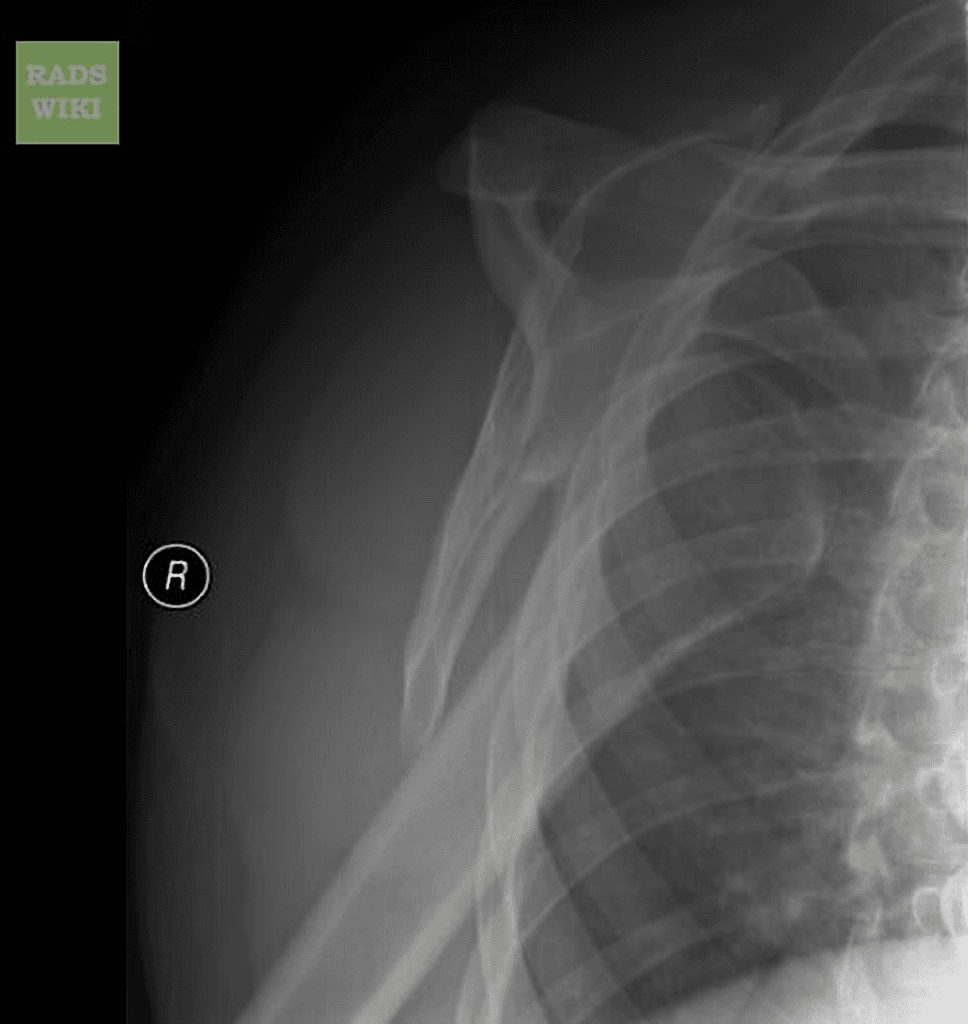

modified axial

Trật khớp vai ra trước

Ngã đập vai trái trong tư thế không thuận lợi, sau đó đau và biến dạng.

Trật khớp chỏm xương cánh tay ra trước trong so với ổ chảo. Không thấy gãy xương hay tổn thương Bankart xương.

Trong bối cảnh chấn thương, việc chụp các bình diện vuông góc là thiết yếu để đánh giá tình trạng trật khớp và các tổn thương kèm theo như gãy xương, biến dạng Hill-Sachs, bất thường Bankart xương và hiếm gặp hơn là tràn máu dịch mỡ khớp. Quy trình này bao gồm một phim chụp thế trước sau kết hợp với thế trục, thế trục biến đổi hoặc thế chữ Y tùy theo tình trạng cụ thể của bệnh nhân.